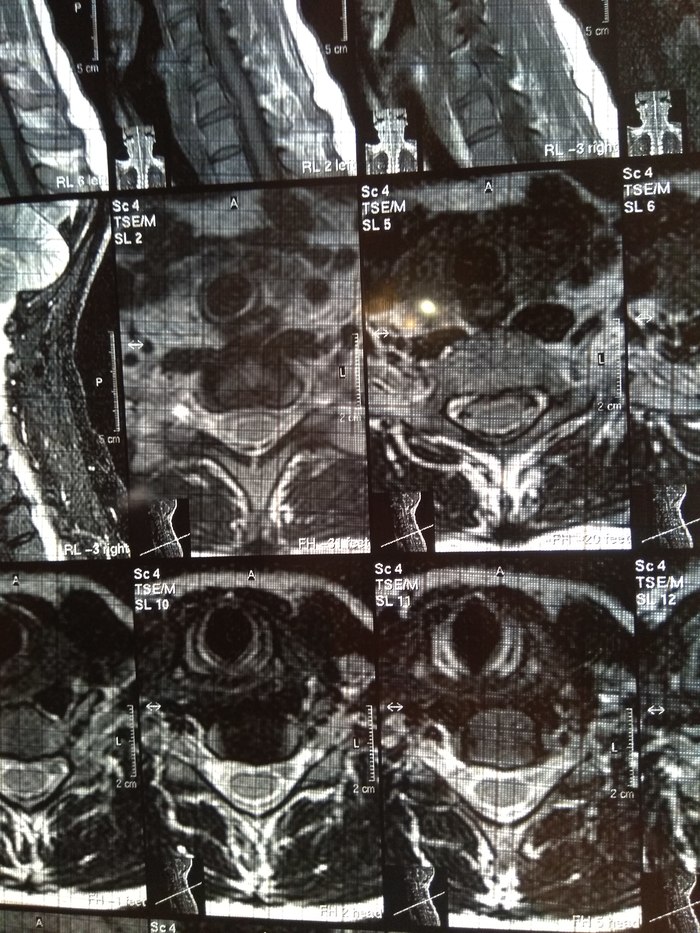

У подруги случилась проблема, тянула с визитом к врачу и в итоге потеряла сознание, вызывали скорую и направили к неврологу. Онемение пальцев на правой руке, сильные боли до судорог и потери сознания. В итоге невролог направил на МРТ и к нейрохирургу, выписали ношение ортопедического воротника, 2 вида уколов и таблетки, названия навскидку не помню. Сказали если через 10 дней не полегчает, то на операцию. Сегодня 5й день, никаких улучшений, рука с каждым днем выше немеет, но подвижность пока в норме. В день по 2-3 раза колет кетонал. Я вот переживаю как бы рука не отказала. Такое может случиться?